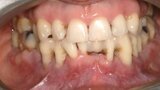

Natychmiastowa implantacja i zaopatrzenie protetyczne pacjentów z zaawansowaną chorobą przyzębia